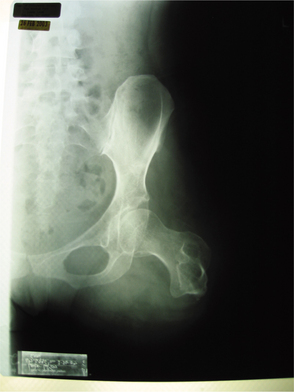

CT scans and especially MRI are used to evaluate the extent of disease. In Fig. 26-7 plain films of a pelvis demonstrate minimal changes that could easily be dismissed as insignificant. The CT scan, however, reveals a large osteosarcoma involving the ilium. More commonly, radiographs show a rapidly growing lesion with poorly defined margins, and a permeated or moth-eaten appearance in the lytic area.

Figure 26-7 Osteosarcoma. A, A subtle sclerotic lesion is seen in the left ilium adjacent to the sacroiliac joint that was initially diagnosed as osteitis condensans ilii, a benign entity. Because of persistent pain, the person returned for a follow-up visit, and a small amount of cortical destruction on the pelvic brim was noted (arrow). B, A computed tomographic scan was performed, which showed a large tissue mass and new bone tumor around the ilium, which is characteristic of an osteogenic sarcoma. (From Helms C: Fundamentals of skeletal radiology: benign cystic lesions, Philadelphia, 1989, WB Saunders.)